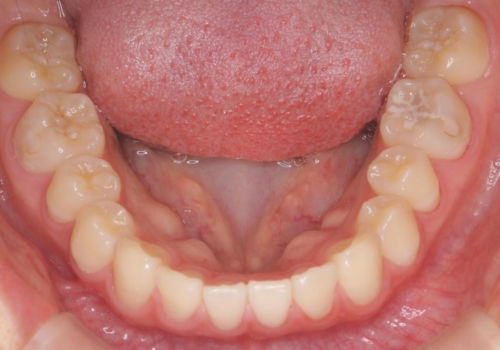

- 10代女性

- ワイヤー矯正

- 9ヶ月

- 前歯のすき間を気にして来院。

全体矯正ではなく部分矯正で治療することになりました。

その代わり、すき間をすべて閉じるのは難しく、両脇の目立たないところに集めて治療終了しています。

低予算、短期間で治療も終了し、大変満足していただきました。

全体矯正をしていないため、就寝時にリテーナー使用は継続していただくことになっています。